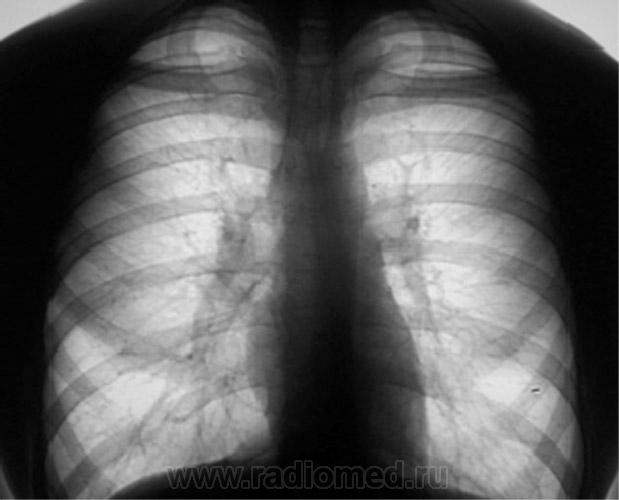

Цифровое стандартное флюорографическое профилактическое исследование (проведено на цифровом флюорографе «Ренекс - Флюоро»). На цифровых флюорограммах, произведенных в прямой, правой и левой боковых проекциях с обеих сторон определяется синдром двусторонней аденопатии. С обеих сторон определяется резкое увеличение и гомогенизация тени корней за счет резко гиперплазированных, в основном, бронхопульмональных лимфатических узлов с довольно чёткими, ровными контурами. Структура тени однородная. На фоне гиперплазированных лимфатических узлов чётко дифференцируются просветы главных бронхов. (Рис. 1, 2, 3). «Поднят архив». Пациент «проходил» флюорографию в 2007 году два раза - первый в январе, как «профилактическую», в июле месяце - при поступлении на работу (Рис. 4). Рентгенологическое исследование проведено по стандартной методике (на РДК на 3 рабочих места -«Вироматик»).

Цифровое стандартное флюорографическое профилактическое исследование (проведено на цифровом флюорографе «Ренекс - Флюоро»). На цифровых флюорограммах, произведенных в прямой, правой и левой боковых проекциях с обеих сторон определяется синдром двусторонней аденопатии. С обеих сторон определяется резкое увеличение и гомогенизация тени корней за счет резко гиперплазированных, в основном, бронхопульмональных лимфатических узлов с довольно чёткими, ровными контурами. Структура тени однородная. На фоне гиперплазированных лимфатических узлов чётко дифференцируются просветы главных бронхов.

(Рис. 1, 2, 3).

«Поднят архив». Пациент «проходил» флюорографию в 2007 году два раза - первый в январе, как «профилактическую», в июле месяце - при поступлении на работу (Рис. 4).

Рентгенологическое исследование проведено по стандартной методике (на РДК на 3 рабочих места -«Вироматик»).